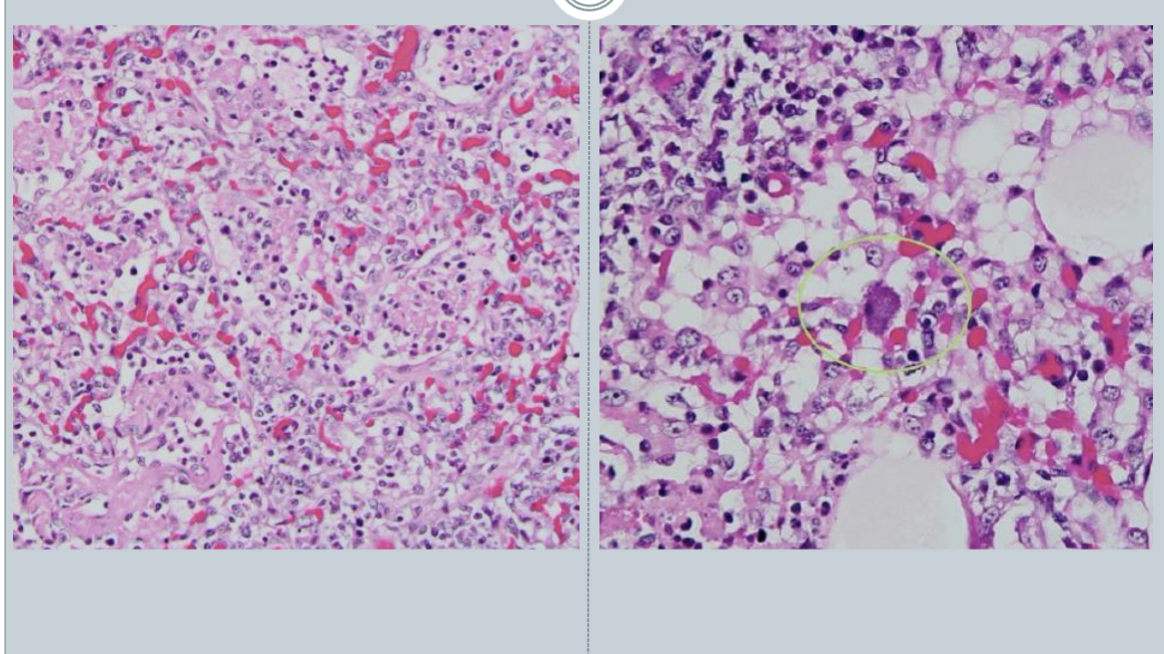

There is a thrombus here.

Mdx: Pulmonary thrombosis

Pulmonary thrombosis

Causes:

1. Heartworm - Difolaria immitis

2. Renal failure associated primarily with glomerular disease.

- antithrombin 3 is one of the main thrombin factors, it is lost through the glomerular filtrate and eliminated in the urine. loss of antithrombin 3 –> pulmonary thrombosis